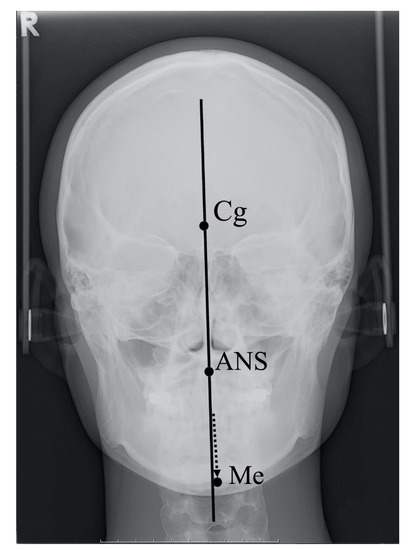

5.2. Facial Asymmetry and Group

5.4. Measurement